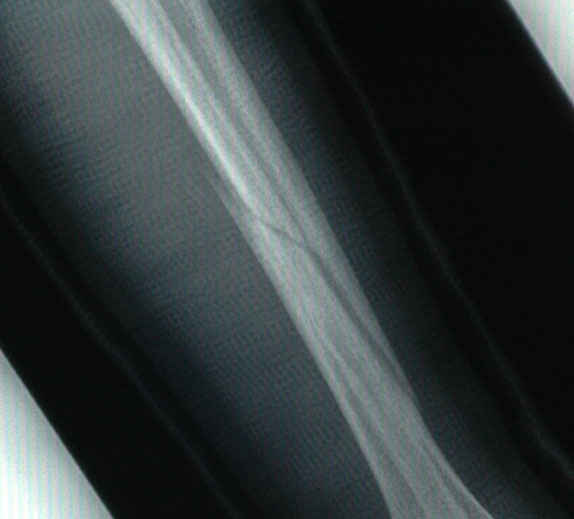

A week later, and the gap has closed up a bit: